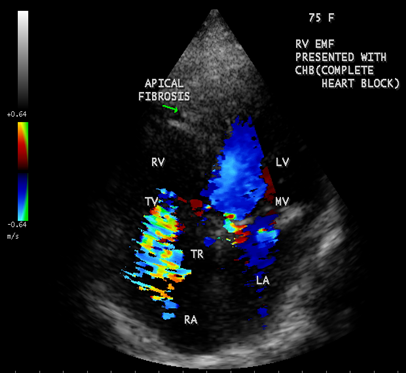

Case 5. Right ventricular EMF presented with complete heart block in a 75- year old female as shown in Figures 21 and 22.

Figure 22: Apical four chamber view showing right ventricular EMF with apical fibrosis in a 75 –year old female

When the endocardium is replaced by collagenous fibrosis (consist of collagen deposition and fibroblast proliferation), the final fibrotic stage is reached after several years of disease activity. Fibrotic obliteration of the apices of the affected ventricles is the hallmark of the disorder and fibrosis involving the papillary muscles and chordae tendineae leading to atrioventricular valve distortion and regurgitation. In the left ventricle, the fibrosis extends from the apex to the posterior mitral leaflet, usually sparing the anterior mitral leaflet and outflow tract and cause PML (posterior mitral leaflet) distortion and regurgitation. Like the peculiar geographical distribution, the fibrotic endomyocardial involvement stops short of the ventricular outflow tract like a ridge [17] as shown in Figures 15,29,31,35 and 44. The fibrotic tissue often creates a nidus for thrombus formation, which can be extensive. Atrial thrombi also occur and the right atrium may be aneurysmally dilated. Aneurysmal right atrium with spontaneous echo contrast was detected in a 32- year old male as shown in Figure 36 [18- Figure 3]. In addition, there are fibrosis and granular septation extending into the underlying myocardial tissue and myocyte hypertrophy is common [19]. Fibrotic process causes tethering of leaflets into ventricular walls and may mimic Ebstein’s malformation as shown in Figure 38[20],[21]. Fibrosis increases the stiffness of the heart, resulting restrictive physiology, AV (atrioventricular) valve regurgitation which has been linked to atrial arrhythmias such as atrial fibrillation as shown in Figures 19 and 20 in a 62-year old female. Atrial fibrillation has been reported in more than 30% of patients with EMF. Fibrosis impairs activation patterns of the conduction system and may provide substrate for wave breaks and reentry [22]. Fibrosis reduces conduction velocity and cause conduction abnormalities like junctional rhythms, heart blocks as shown in Figure 21 and 22 in a 75-year old female and atrioventricular conduction delay [23].